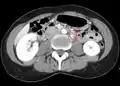

ضغط الوريد الكلوي الأيسر (ملحوظ بالسهم) بين الشريان المساريقي العلوي (أعلاه) والشريان الأورطي (أدناه) بسبب متلازمة كسارة البندق.